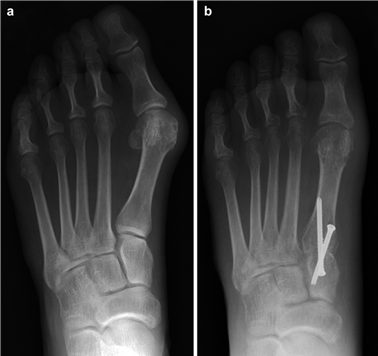

Clinical & Radiographic Imaging Archive

Clinical Image